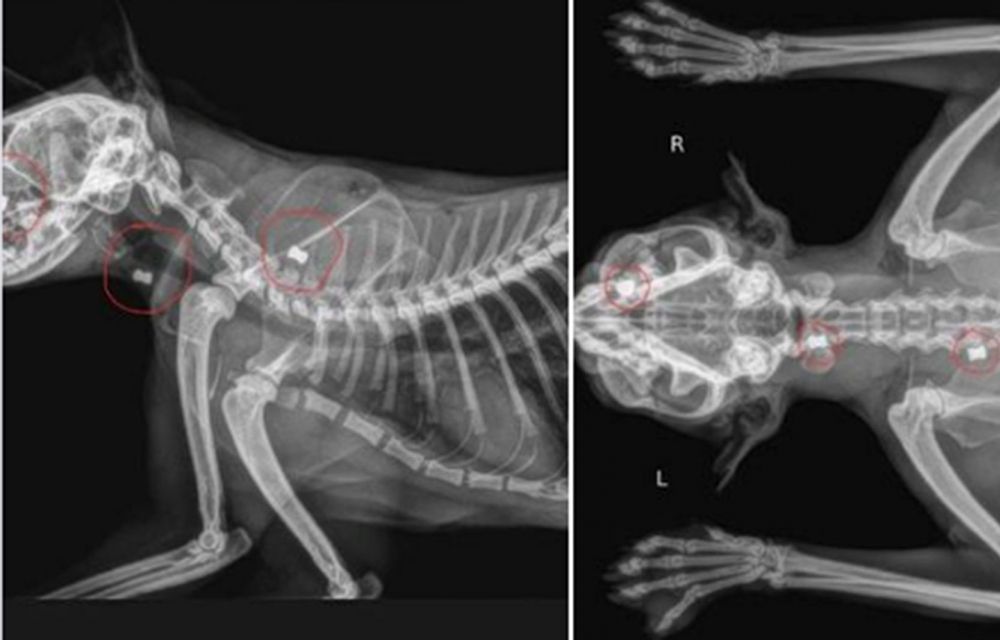

Per ara, tot s’ha centrat amb l’atenció de l’animal, que ha estat operat d’urgència en una clínica veterinària del país per poder-li ser extrets tres balins que tenia a l’interior del cos especialment a la zona del cap. Un dels trets li hauria passat entre els dos ulls. El felí es debat entre la vida la mort i res, ara per ara, garanteix que pugui sobreviure.